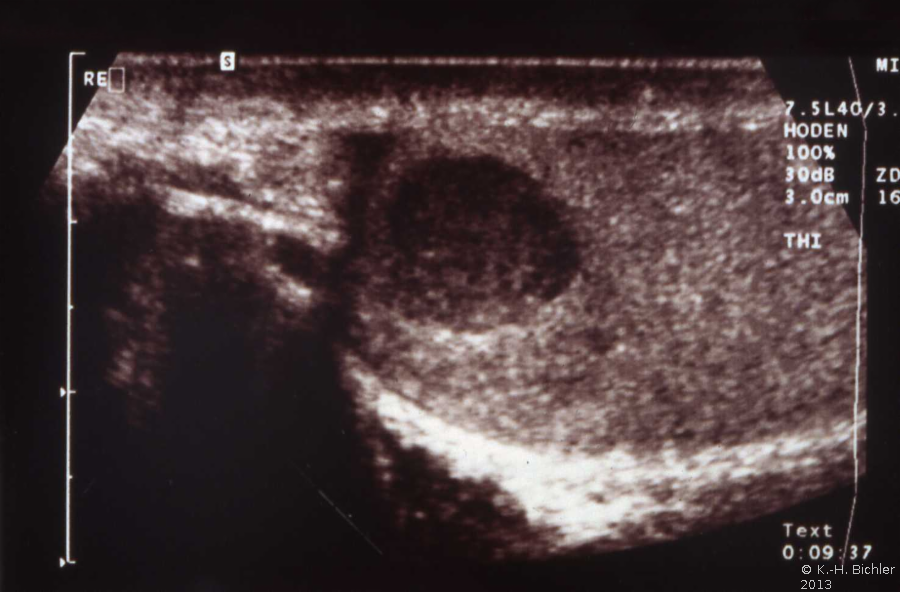

Bei dem jüngeren Erwachsenen war eine umschriebene Verhärtung bei der Palpation und ein tumorverdächtiges Areal in der Sonographie aufgefallen (Abbildung HG1). Die Hodenfreilegung und Entnahme einer Gewebsprobe ergaben in der histologischen Untersuchung ein Seminom sowie Seminoma in Situ (s. Abbildung 3).